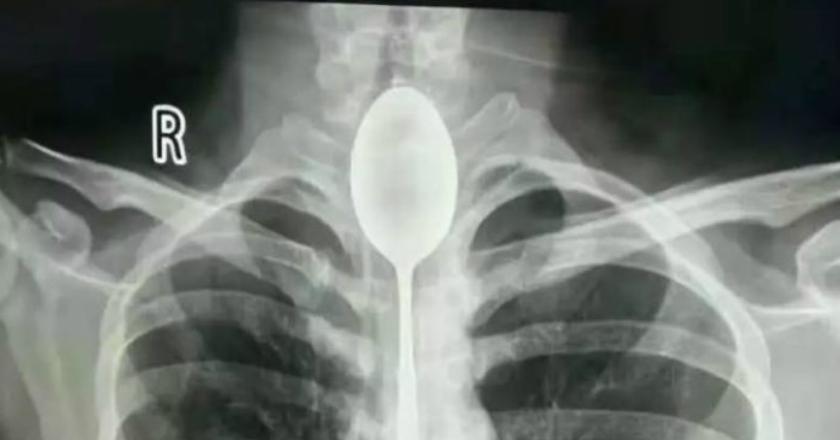

Sendok sepanjang 20cm yang diangkat dari tenggorokan Zhang. (Foto: Xinjiang Coal Mine General Hospital)

Pantau.com - Seorang dokter mengangkat sebuah sendok dengan panjang 20 sentimeter dari kerongkongan seorang pria di China. Pria yang berusia 20 tahun yang diketahu bernama Zhang telah menelan sebuah sendok sejak 2017 lalu.

Hingga akhirnya, sendok tersebut menjadi masalah yang menyebabkan seperti mendapatkan pukulan pada bagian dada. Ia juga merasakan kesulitan bernapas dan dadanya sakit. Ia kemudian memutuskan untuk melakukan x-ray dan mengejutkan dokter dengan hasilnya.